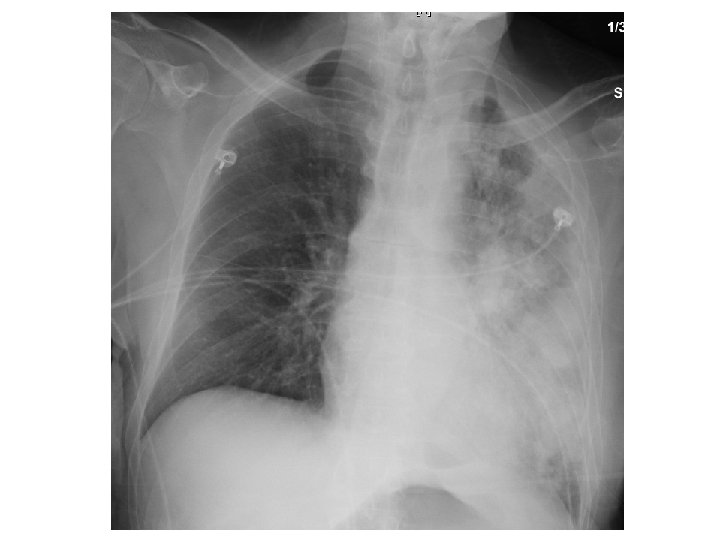

Physical exam • HR 117 • Vital signs including RR and O 2 Sat. were normal range (12 -18/ 96 -100%) • Respiratory: Positive egophony on left lung. • Gastrointestinal: Diffusely tender to palpation without rebound/ guarding, no masses

ER work-up • Abdominal XR = No obstruction/ air fluid level Atelectasis with central bronchial obstruction

CT Chest • Multiple cavitary lesions • Largest left lung apex 3. 8 x 4. 7 cm with nodular thickened wall • Smaller cavitary lesions in L lung base • R lung: smaller areas of ground-glass opacities with areas of tree in bud appearance.

A few hours post-bronchoscopy… • • Tachypneic with RR 30 s Tachycardic to HR 150 s Hypoxic w/ SPO 2 92 on 4 L NC Accessory muscle use. Crackles, most prominent over left upper lung field. Decreased breath sounds, more prominent on left side • ABG 7. 5 / 22 / 65 / 20 / 93, lact 3. 4 • Transferred to MICU for new sepsis secondary to HCAP ; Rx vancomycin and cefepime